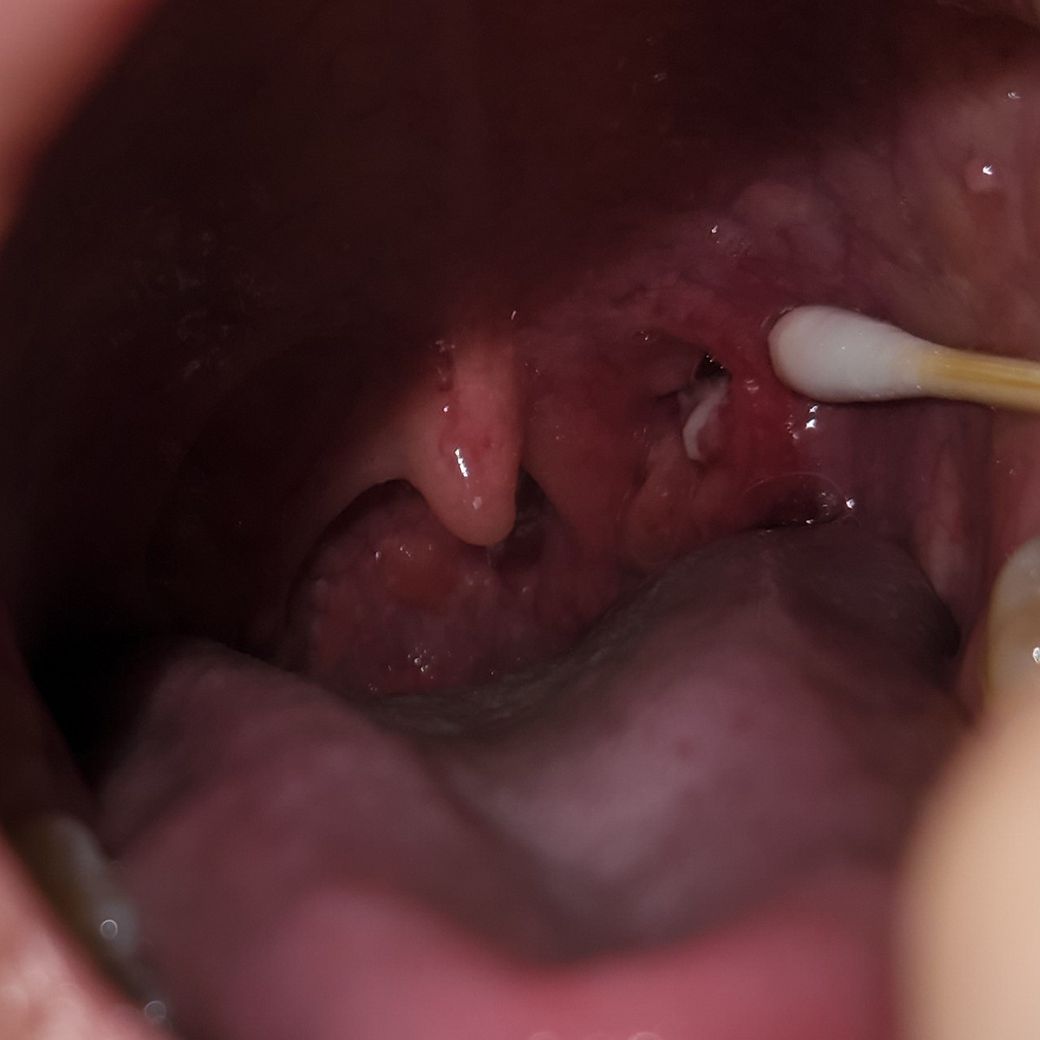

한쪽 편도에 흰색 무언가가 보이고 아픈데 뭔가요?

한쪽 편도가 부은 느낌이 나고, 무언가를 삼킬때 부은 느낌과 함께 통증이 느껴집니다. 혹시 편도결석 같은건가 해서 면봉으로 건드려봤는데 뭐가 나오지는 않고 약간 살같은 느낌이 납니다. 전에는 이런적이 없었습니다.

편도결석 혹은 편도선염 같은 것일까요? 염증 반응일까요?

현재 사진만으로 파악은 어려우나 편도 주위 농양을 의심해 볼 수 있을 것 같습니다. 심한 경우 외과적 절제가 필요할 수도 있으니 이비인후과에 내원하시어 진료를 받아보시는 것이 좋겠습니다.

편도 염증일 가능성도 있습니다. 진료를 보시는 것이 가장 효과적이지만 여의치 않다면 소염진통제를 복용하시는 것이 도움이 되겠습니다. 면봉으로 자극을 하는 것은 오히려 증상을 악화시킬수 있기에 가급적 면봉으로 누르지 않도록 주의하시기 바랍니다.

• 사진의 소견만 보아서는 확실하게 판단하기 어렵지만 편도염이나 편도 결석 소견은 아닙니다. 마치 궤양성 병변 같아 보이며 아무래도 구내염 증상일 가능성이 높아 보입니다. 우선은 컨디션을 잘 관리하면서 경과를 지켜보면 스스로 호전될 가능성이 높아 보입니다. 따로 약물 복용이 필요해 보이지는 않으며 가글을 해주는 것이 도움이 될 수 있겠습니다. 만약 차도가 없다면 이비인후과 검진 후 처방을 받으시길 권고드립니다.

편도선염 같습니다. 아마 해외에서도 소염 진통제는 구하실 수 있을텐데 약을 드시면서 지켜보셔야 될 것 같습니다. 만약 증상 호전이 안되면 항생제 치료가 필요할 수 있어서 병원에 가보시는 것이 좋겠구요.